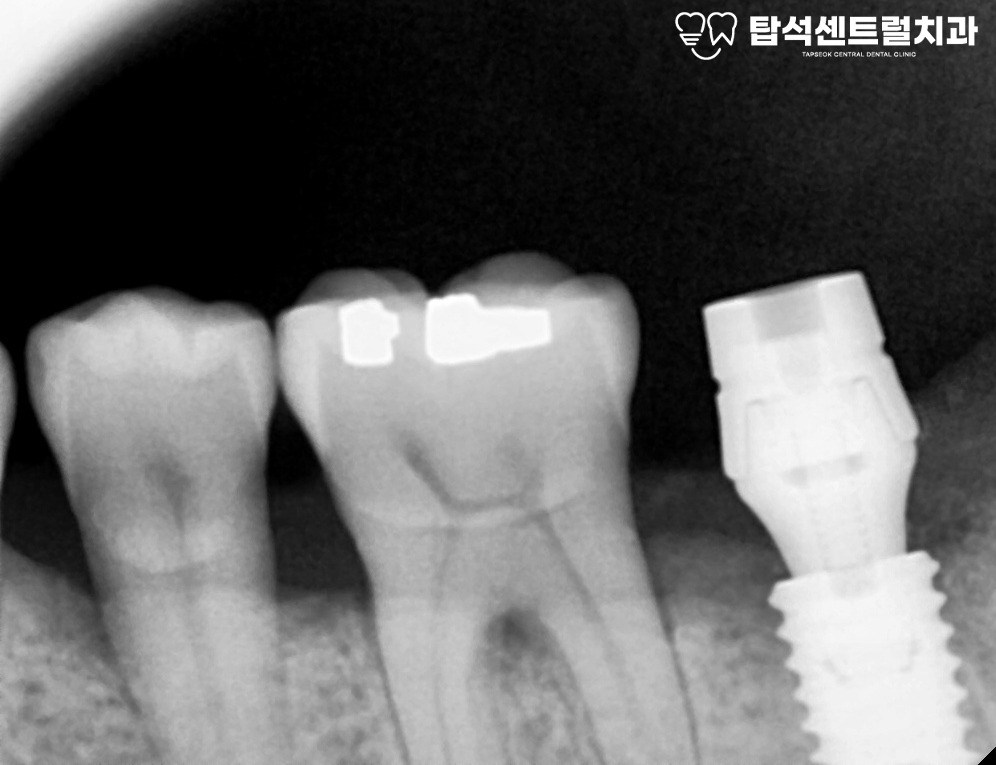

아랫니 부위에 즉시 임플란트 식립과

발치와 보존술을 진행하기로 합니다.

당일 아랫니는 발거 후

픽스처를 심는 방식으로 진행됩니다.

즉시 식립은 발치와 식립을 한 번에 해결하여

치료 기간을 단축시킬 수 있다는 특징이 있습니다.

다만 뼈의 상태가 충분히 건강해야 하고

초기 안정성을 확보할 수 있어야 가능합니다.

이후 충분한 시간이 흘러,

아래턱에 2차 수술 후

형태에 맞는 크라운을

올려두었습니다.

3개월 후 임플란트와 뼈가 잘 결합되면

크라운을 올려 치료를 종결합니다.